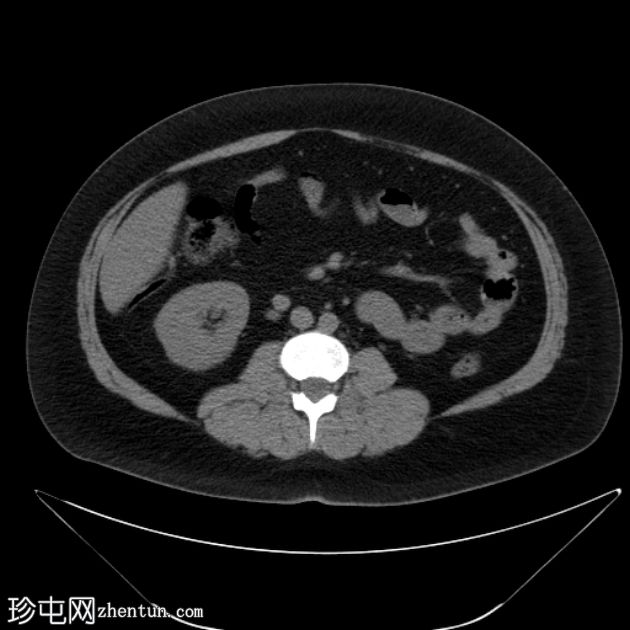

CT扫描

轴位

平扫

肝下阑尾,无急性炎症改变。

左肾切除史。

未见右肾、输尿管或膀胱结石。无反压改变。

肝下阑尾是一种罕见的解剖变异,阑尾位于肝脏下方,通常是由于胚胎发育过程中肠旋转不全所致。

肝下阑尾炎是指阑尾和盲肠位于“肝下”位置时发生的炎症,如本例所示。

肝下阑尾炎在临床上常与肝胆疾病相似。